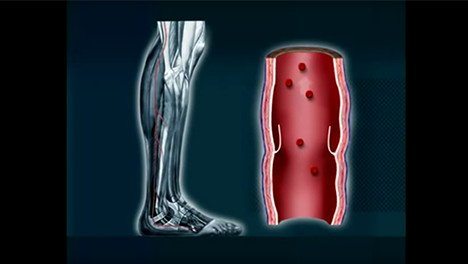

Deep vein thrombosis (DVT) is a serious, but treatable condition that occurs when a blood clot forms deep inside the veins of your body, typically in the lower leg, thigh or pelvic area. Blood clots affect almost 900,000 people each year in the United States and can lead to pulmonary embolism (PE), a potentially fatal condition in which the blood clot can break off and block blood flow to the lungs.1 Without adequate blood flow, damage to the lungs and other organs of the body can occur, requiring prompt medical attention.

Despite serious complications, DVT can be treated if detected early. Certain treatments may work for some patients, but not others. A vascular specialist may recommend treatments that prevent the blood clot from enlarging and moving to the lungs or other therapies to dissolve the clot right away. These treatments may include:3 Photos of DVT Treatments